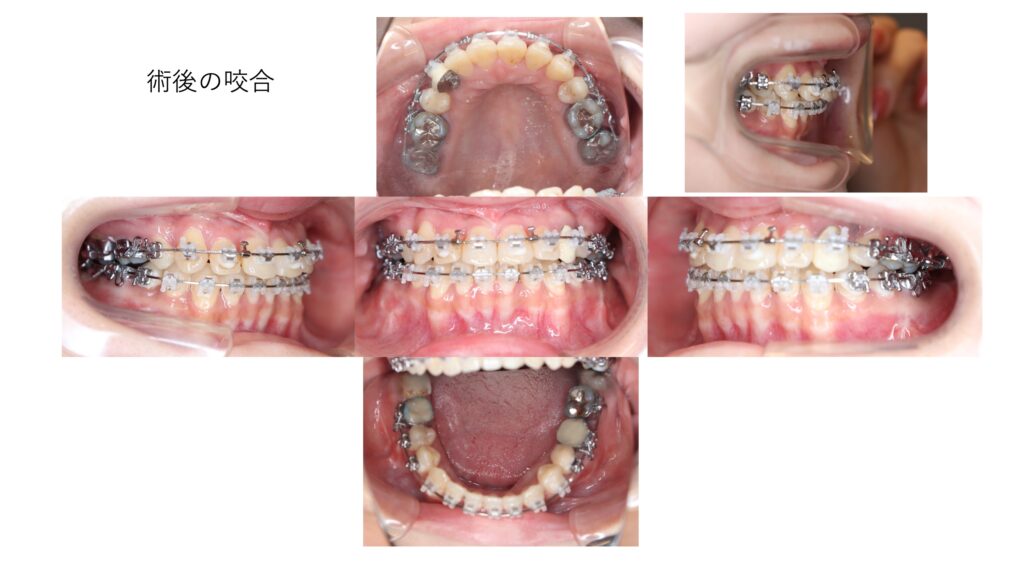

噛み合わせの写真では、上あごの歯の中心(正中)と、下あごの歯の中心が一致しており、緊密な咬合が得られています。